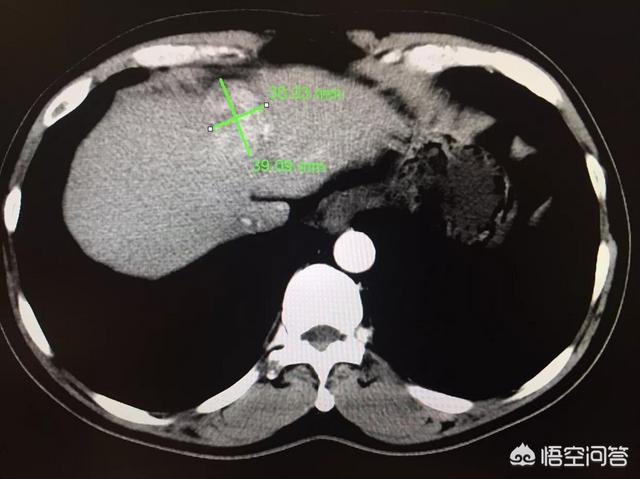

Il s'agit d'un patient de 55 ans atteint d'une hépatite B chronique. L'examen physique et l'échographie ont révélé une occupation du foie, un taux élevé d'AFP et un cancer du foie très typique à l'imagerie. Il est important d'effectuer des contrôles médicaux réguliers si vous avez une hépatite B !

Au scanner, un carcinome hépatocellulaire typique se présente sur l'imageEntrée rapide, sortie rapideLa manifestation de ce phénomène doit être réalisée avec un renforcement pour le voir. Le diagnostic de cancer du foie est très fiable lorsque l'on voit des nodules de ce type. Le carcinome hépatocellulaire est également la seule maladie qui peut être traitée sans qu'un diagnostic pathologique soit confirmé. Le diagnostic est basé sur la typicité de l'imagerie et sur les antécédents d'hépatite B. L'ablation interventionnelle ou l'embolisation peuvent alors être envisagées pour le traitement.